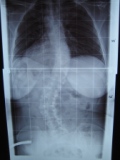

diese Woche hatte ich mein erstes Kontrollröntgen in meinem nun nicht mehr ganz so neuem Rahmouni Korsett! Habe mit Korsett eine Korrektur von lumbal 52° auf 30° und thorakal von 44° auf 23°. War ganz happy als ich meinen Rücken auf dem Röntgenbild gesehen habe.

- Röntgen mit Korsett LW30° BW23°

- IMG_2871.JPG (18.57 KiB) 3261 mal betrachtet